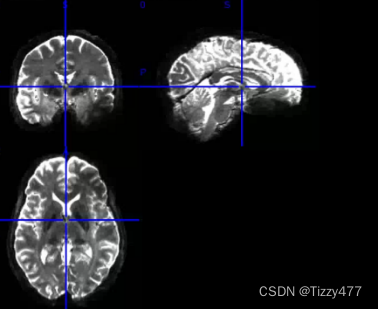

4.创建FA和MD图——使用dtifit函数

dtifit -k $dir_temp/data.nii.gz -o $dir_temp/data -m $dir_temp/nodif_brain_mask.nii.gz -r $dir_temp/bvecs -b $dir_temp/bvals --save_tensor